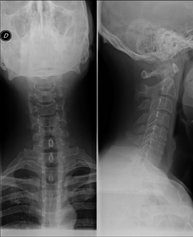

- RX Columna cervical

Tècnica que usa els raigs X a través de la qual s'obtenen imatges de la columna cervical per al seu estudi. Indicacions: traumatisme, dolor cervical. - RX Columna dorsal